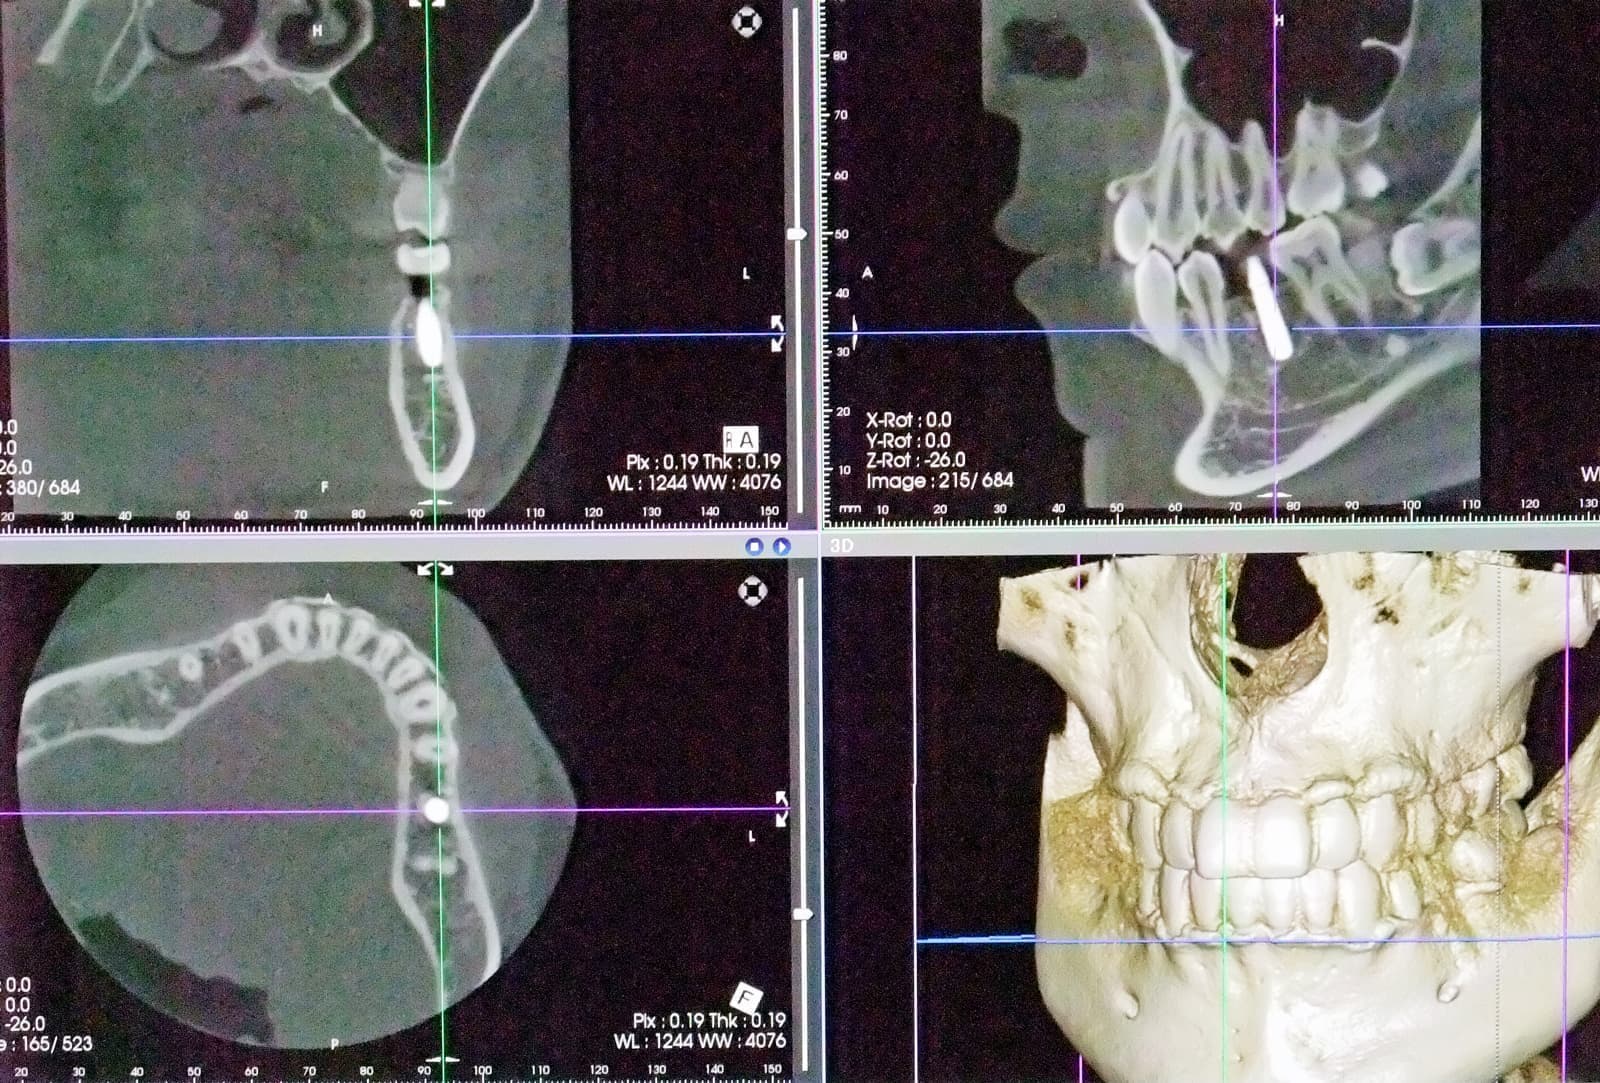

CT 3D デジタルレントゲン

HCT 3D Roentgen

img_4253.jpg ctga_20201009231644597.jpg di3d.jpg

高精細で被爆量も少なく安心

当院では、歯科用CT3Dデジタルレントゲンを活用し、身体への負担を少なく、状況を詳しく把握し、的確な治療を提供出来るよう心掛けております。

CTデジタルレントゲンに使われているX線センサーは高感度で照射時間も短く、より低線量でのレントゲン画像の取得が可能となり、お子様にも安心です。

インプラント手術や歯周病治療、歯列矯正治療、歯の根の病気に関係する治療の正確な診断、治療計画には、3DCTによる撮影が欠かせません。

例えば、親知らずの抜歯や骨内に埋伏している過剰歯の抜歯等、正確な位置や神経や血管等との距離を3次元的に把握することで負担の少ない安心な処置が行えます。